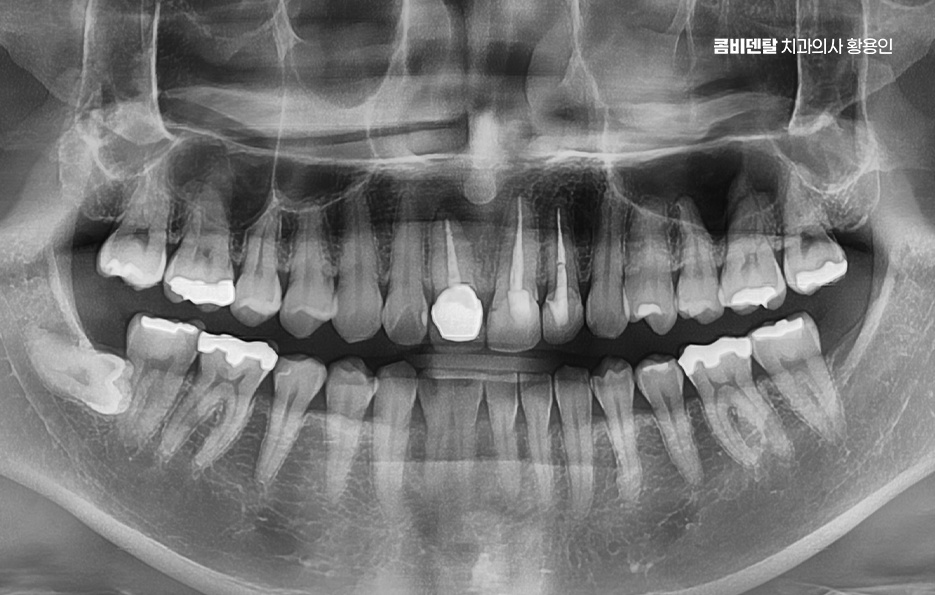

이처럼 과거에 치료를 받았던 보철물은 시간이 오래 지난 후에 문제가 발생할 수 있지만 한참 안아프고 별다른 문제가 없었다는 이유로 잊고 지내다 보면 나중에 문제가 커지는 경우가 있는데요

즉 앞니에 오래된 보철물이 있다면 언젠가는 꼭 점검해 봐야 하는 시점이 오게 되지만 겉보기엔 괜찮아 보일 수 있어요.

색도 아직 흰 편이고, 기능적으로도 문제없이 사용하고 있을 수도 있는데 보철물이 오래됐다는 건 그 안쪽이나 주변에 문제가 숨어 있을 가능성이 높다는 뜻이기도 하고 특히 앞니처럼 심미성과 기능이 모두 중요한 부위는 작은 변화도 크게 느껴지고 문제를 오래 방치하면 결국 재신경치료나 발치로 이어지는 경우도 있어요

앞니는 웃을 때, 말할 때 먼저 보이는 자리여서 과거에는 심미성만 우선해서 치료를 하거나, 그 당시 기술로 가능한 선에서만 보철을 해둔 경우가 많은데 시간이 지나면 잇몸이 내려가면서 보철물 가장자리가 드러나거나 회색 선이 드러나는 경우나 2차 충치 등의 문제가 나타날 수 있었어요

이런 경우 처음엔 잇몸이 붓거나 피가 나는 가벼운 증상으로 시작될 수 있지만 그 아래에서는 이미 보철물 안쪽 치아가 썩고 있거나, 보철물 아래 충치가 진행됐을 수 있으며 특히 오래된 보철물은 접착제가 이미 닳아 있거나 밀착력이 떨어져 있어서 세균이 쉽게 침투할 수 있어서 이런 식의 2차 충치는 눈으로 보이지 않기 때문에, 문제가 꽤 심각해졌을 때야 느끼게 되는 경우가 많은 거예요

문제가 심해지면 결국 신경에까지 세균이 도달해서 통증이 생기고 찬물에 시리거나, 저리듯이 쑤시는 느낌, 잇몸에 작은 뾰루지가 생기는 경우도 있으며 그냥 손가락으로 눌렀을 때 묵직한 압통이 있다면 이미 신경치료가 필요한 상태일 가능성이 높아지고 이런 경우엔 기존 보철물을 제거하고, 내부 충치 상태를 확인한 뒤, 신경치료부터 들어가야 할 수 있었어요